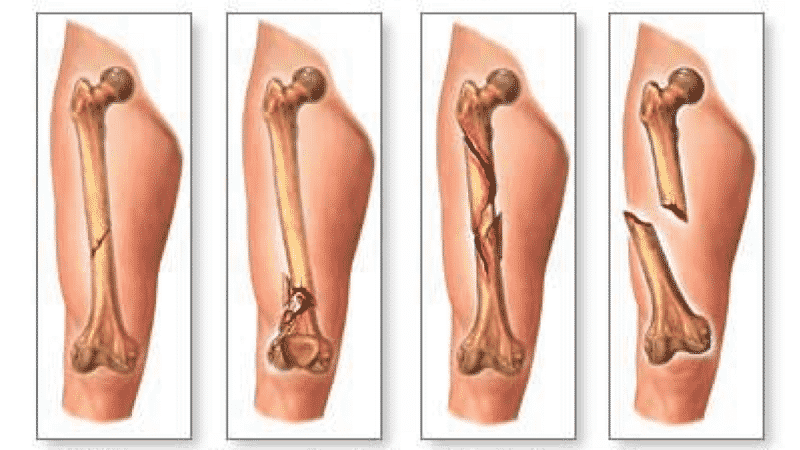

Трещины в костях образуются в результате прямого воздействия – удара, неудачного падения. Тканям не хватает прочности, чтобы выдержать силу, но опорная функция кости сохраняется. При переломах, наоборот, происходит смещение обломков. На одном элементе скелета может возникнуть одна или несколько трещин, которые формируют косые, прямые или спиралевидные линии.

Основной признак перелома – смещение костной ткани, деформация либо укорочение конечности, чего не бывает при трещинах. Болевые ощущения настолько сильны, что человек не может совершать даже малейшие движения.